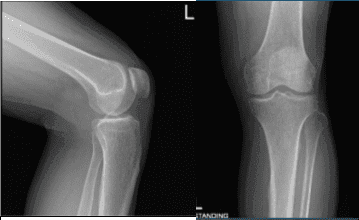

Se presentaron informes de radiografías y no hay cambios degenerativos significativos. El paciente deseaba proceder con la inyección para reducir el dolor y la inflamación. Tras una preparación estéril, se inyectaron 7 cc de lidocaína al 1% y 80 ml de Depo-Medrol en la rodilla izquierda.

AP y Vista de Latera